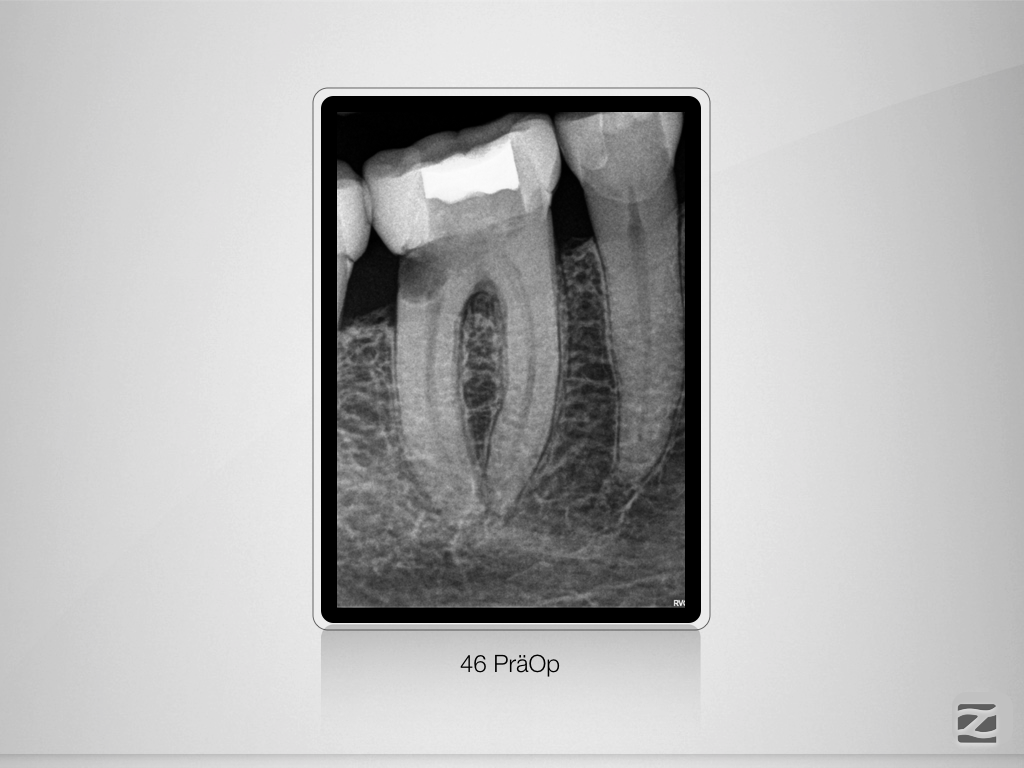

Tiefe Gabelung mit 90 Grad nach distal